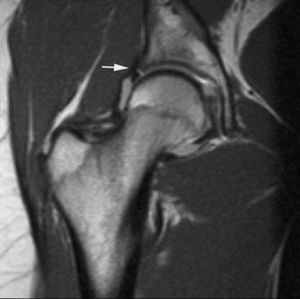

La RMA es una técnica con mayor eficacia diagnóstica en la valoración de las roturas meniscales recurrentes. Después de meniscectomías parciales, la capacidad de diagnosticar roturas recurrentes depende de la cantidad de menisco extirpado. Cuando la resección meniscal es menor del 25% los criterios de rotura en RM son los mismos que en la rodilla no operada --la fiabilidad de la RMA es similar a la de la RM en estos casos--. Cuando la resección es mayor del 75% la clínica del paciente no se asocia a las rerroturas meniscales. En los casos de resección entre el 25 y el 75% los criterios de rerrotura se basan en la introducción de contraste en el remanente meniscal (fig. 6)1,15,16.

Fig. 6.--Rerrotura de asta posterior del menisco interno. A, B) Corte coronal potenciado en T1 y corte sagital de RMA potenciado en T1 con técnica de supresión grasa en los que se observa introducción del contraste en el defecto meniscal.